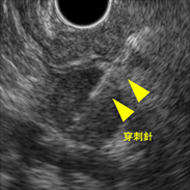

超音波内視鏡下吸引針生検(EUS-FNA)

EUSでの観察で、穿刺適応病変があった場合、EUS-FNAによって病理検査が可能です。 従来細胞採取が困難であった膵体尾部腫瘍や粘膜下腫瘍、リンパ節などを対象にEUSで 病変を視認しつつ19~25Gの穿刺針を用いて生検します。 当科では1泊2日の入院での検査を基本としています。

膵尾部腫瘍に対するEUS-FNA